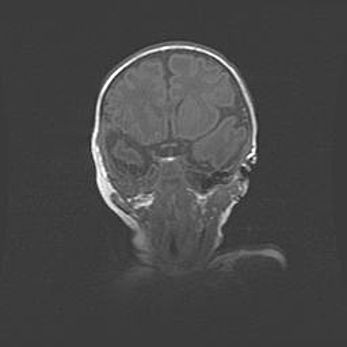

Открытая гидроцефалия.

Возраст: 9 месяцев 12 дней

Вес: 6800 г

Пол: мужской

Окружность головы: 41,5 см

Срок гестации: 28 недель

Гидроцефалия головного мозга у новорожденных имеет характерный признак: опережающий рост окружности головы приводит к визуально хорошо определяемой гидроцефальной форме сильно увеличенного в объёме черепа. Детские неврологи определяют следующие симптомы гидроцефалии у грудничков: выбухающий напряжённый родничок, частое запрокидывание головы, смещение глазных яблок к низу.